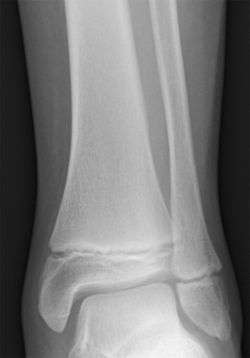

The epiphyseal plate (or epiphysial plate, physis, or growth plate) is a hyaline cartilage plate in the metaphysis at each end of a long bone.

The plate is found in children and adolescents; in adults, who have stopped growing, the plate is replaced by an epiphyseal line.

Salter–Harris fractures are fractures involving epiphyseal plates and hence tend to interfere with growth and height.